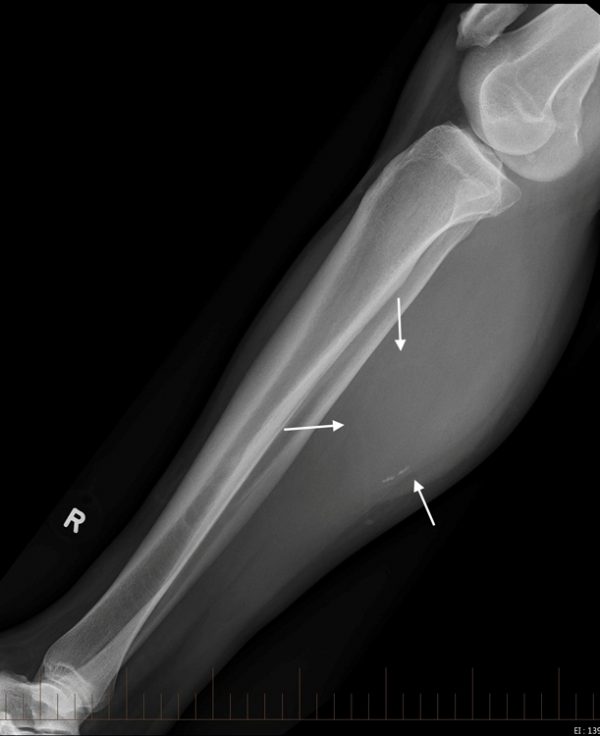

Tụ máu cẳng chân

Tụ máu cẳng chân - Ảnh 3

» Thông tin: Nam giới – 41 tuổi.

» Lâm sàng: Sưng đau cẳng chân / Chấn thương cẳng chân 15 năm.